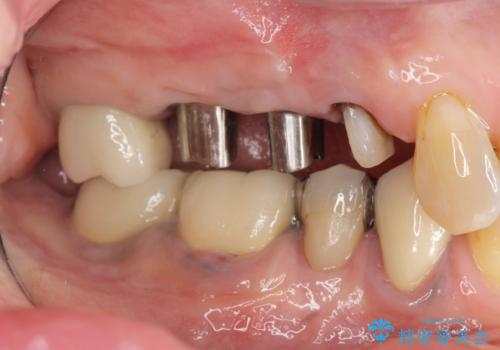

過大な咬合力で破折した奥歯 インプラント治療で咬合機能の回復

- 「噛むと歯に痛みを感じる、噛めない。」、と痛みの改善を希望され来院されました。

X線写真検査を行ったところ、ブリッジ支台の歯が破折(割れている状態)し抜歯が必要な状態です。

抜歯をしたのちしっかりと咬合力を回復し前後の歯を守るためにも、入れ歯やブリッジではなくインプラントによる咬合機能回復を計画します。